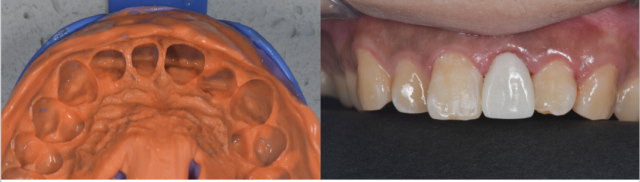

术前口内照片 A.术前唇面照;B.术前黑背板照;C.术前舌侧照;D.术前牙齿宽度测量;E.牙周基础治疗后的比色照;F.偏振光照看牙齿纹理

术中治疗 A.桩道预备完成;B.纤维桩试合;C.充填树脂水门汀;D.纤维桩就位

A.树脂核堆塑;B.牙体预备;C.根尖保留4mm根充物植入纤维桩的术后影像;D.两中切牙近远中比例检测;E.11去龋;F.11树脂充填,11、22邻面去釉抛光

牙体预备排龈 A.唇面观;B.?面观